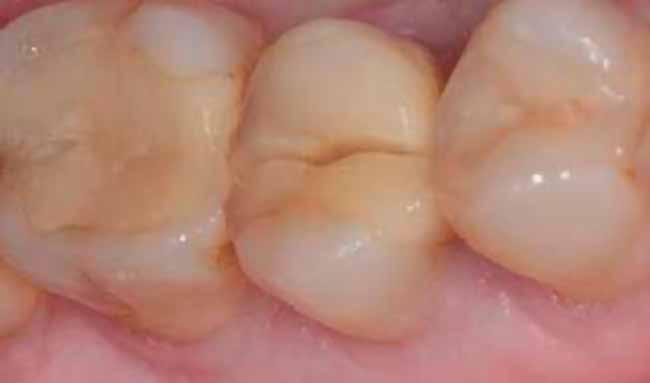

A végleges protetikai ellátást három hónappal az implantációt követően kezdtük meg. Az implantátumok gyógyulása panasz- és tünetmentes volt. Hagyományos, zárt kanalas A-szilikon lenyomatot vettünk (8. a–c ábrák). Egy esetben a gingivális emergenciát sikerült nagy pontossággal lemintázni fényre kötő folyékony kompozit segítségével (Master Flow, Biodinamica; 9. a–c ábrák). Három lítium-diszilikát és egy monolitikus cirkonkorona készült (10. a–b. ábrák), amelyek cementtel rögzültek a végleges protetikai fejeken (Dual RelyX™ U200, 3M; 11. a–b ábrák).

10. a ábra: Végleges lítium-diszilikát koronák. – 10. b ábra: Végleges monolitikus cirkónium-dioxid korona. – 11. a–b ábrák: Klinikai megjelenés tizenkét hónap elteltével. 12. a–b ábrák: Tizenkét hónapos kontrollröntgen-felvételek.